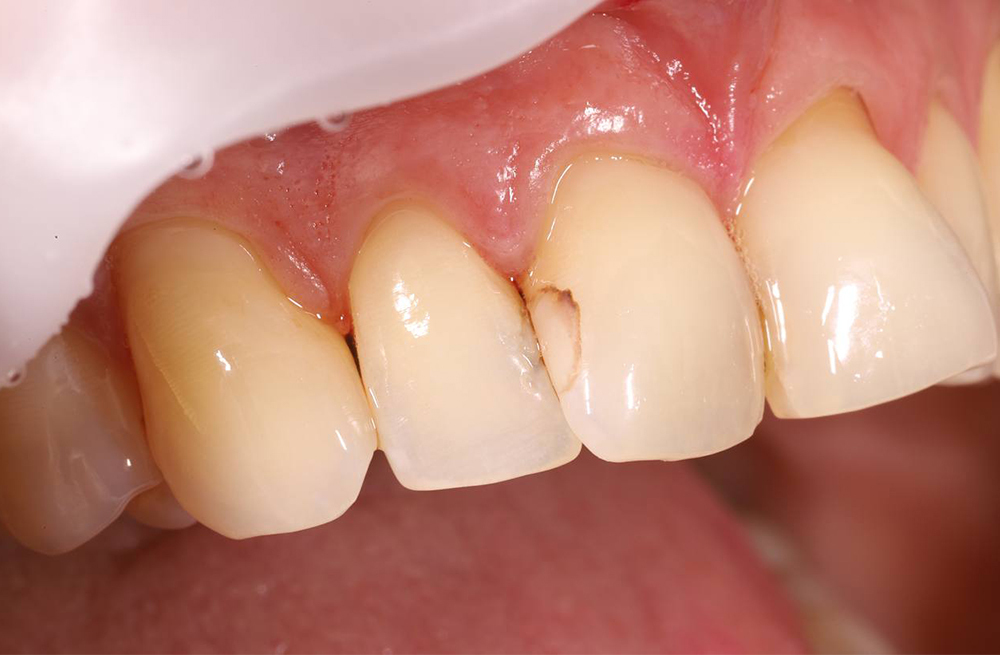

Лечение контактного кариеса передних зубов